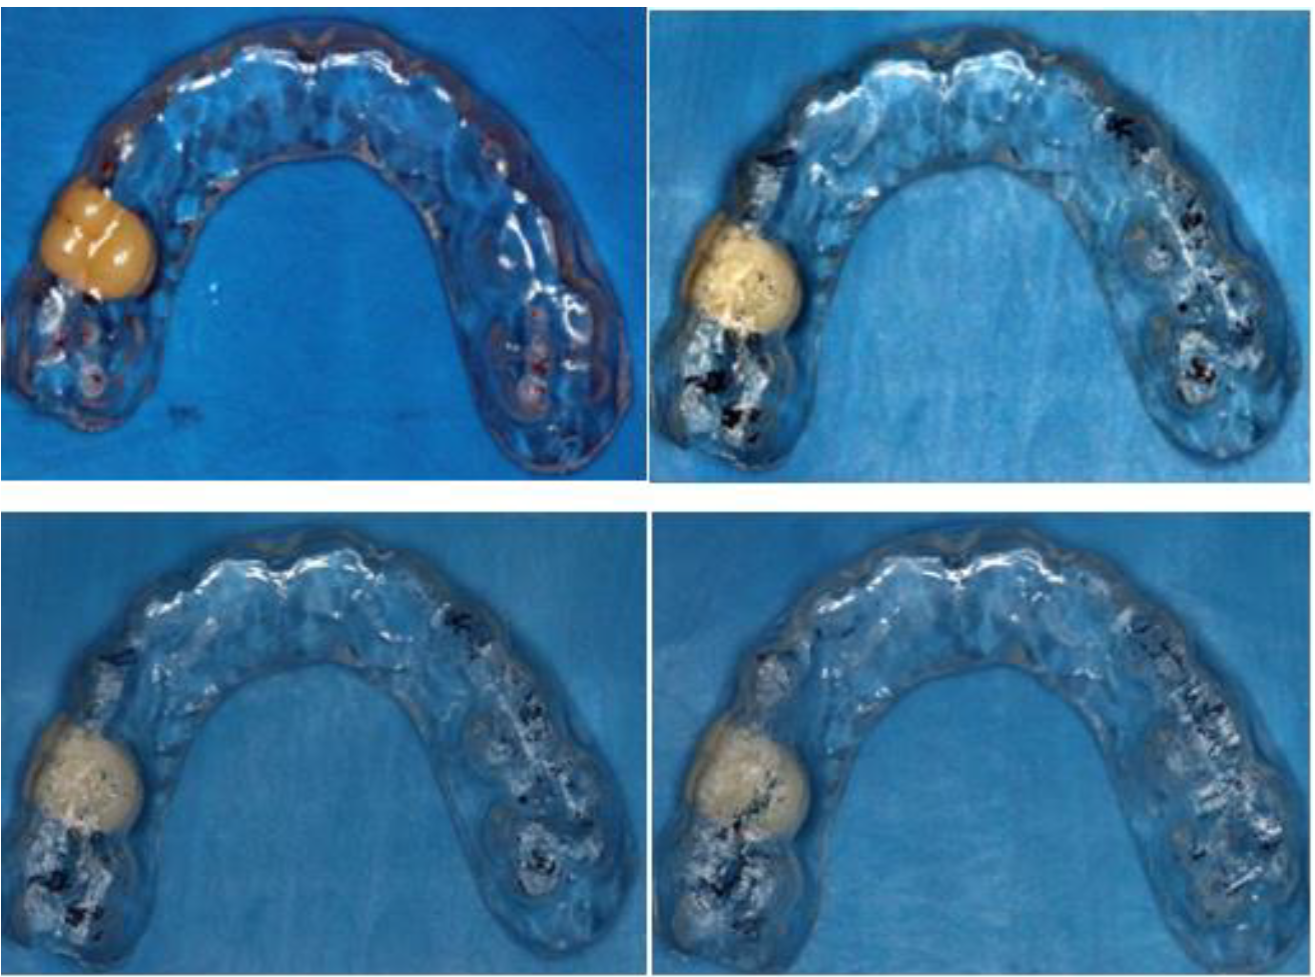

Las placas de mordida en niños son dispositivos interoclusales removibles, que cubren todos los dientes de uno de los arcos maxilares y que necesita estar bien estable y ajustada para funcionar correctamente. Esta es una placa de acetato, con un grosor de 1,5 a 3mm, el cual debe s er usado por 90 días y se debe realizar ajustes con papel articular de 12mm una vez al mes para conseguir estabilidad funcional neuromuscular.

Esta placa de mordida tiene las propiedades de poseer efectos reversibles, al alterar la propiocepción de músculos, no interfiere en el crecimiento de los maxilares, ayuda a reposicionar la mandíbula en relación céntrica, protege a los dientes contra la af racción y el desgaste, disminuye la actividad muscular, evita la erupción atrasada o impactación de los dientes permanentes y evita las mal formaciones de la dentina y el esmalte.

Con relación al Plan de Tratamiento, se recomendó realizar cambios de comportamiento, se mencionó indicaciones sobre la terapia del sueño, se encaminó a realizar más actividad física y se instaló la placa de mordida que en este caso se colocó un diente de acrílico para servir como mantenedor de espacio de la pieza ausente. Después de elaborada la placa de acetato, se realiza el ajuste de la placa en boca para que los puntos oclusales sean estables y equilibrados de forma bilateral.

Figura 14. Ajuste oclusal bilateral para establecer puntos de contactos estables y equilibrados. Después de realizar los controles oclusales y la instalación de la placa se realizaron controles pos-instalación a los 15,30,60 y 90 días.